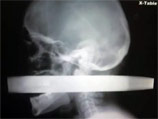

В больницу Линна пришлось везти в сидячем положении, поскольку торчавшие у него из лица и шеи куски трубы диаметром больше 5 сантиметров не позволяли лечь. В длину же балка, после того, как ее обрезали, составляла свыше 15 сантиметров.

В больнице, куда доставили травмированного мужчину, был сразу же сделан рентгеновский снимок его головы. До сих пор видели его только врачи, ни пациент, ни его семья, ни кто-либо из посторонних даже не представлял, насколько страшно все выглядело в ту минуту. Снимок обнародован только спустя семь месяцев, и не просто так - в клинике, где у него извлекли трубу, на днях состоялось ежегодное мероприятие, на котором описывают самые удивительные случаи спасения жертв чудовищных травм.